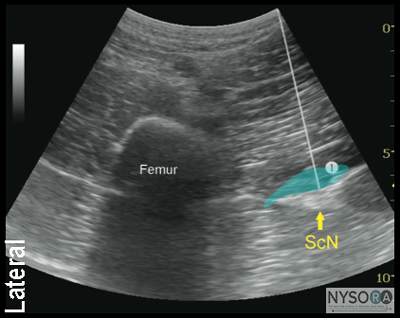

Technique With the patient in the proper position, the skin is disinfected and the transducer positioned so as to identify the sciatic nerve. If the nerve is not immediately apparent, sliding and tilting the transducer proximally or distally can be useful to improve the contrast and bring the nerve 'out' of the background from the musculature. Finally, if the patient is able to dorsiflex and/or plantar flex the ankle, this maneuver often causes the nerve to rotate or otherwise move within the muscular planes, facilitating identification. Once identified, the needle is inserted in-plane or out of plane (more common in our program) from the medial aspect of the thigh and advanced toward the sciatic nerve (Figure 1-5). If nerve stimulation is used (1.0 mA, 0.1 msec), the contact of the needle tip with the sciatic nerve is usually associated with a motor response of the calf or foot. Once the needle tip is deemed to be in the proper position, 1 to 2 mL of local anesthetic is injected to confirm the adequate distribution of injectate. Such injection helps delineate the sciatic nerve within its intramuscular tunnel, but it may displace the sciatic nerve away from the needle. Improper spread of the local anesthetic or nerve displacement may require an additional advancement of the needle. When injection of the local anesthetic does not appear to result in a spread around the sciatic nerve, additional needle repositions and injections are necessary.

In an adult patient, 15 to 20 mL of local anesthetic is usually adequate for successful blockade (Figure 1-6). Although a single injection of such volume of local anesthetic suffices, it may be beneficial to inject two to three smaller aliquots at different locations to assure the spread of the local anesthetic solution around the sciatic nerve.